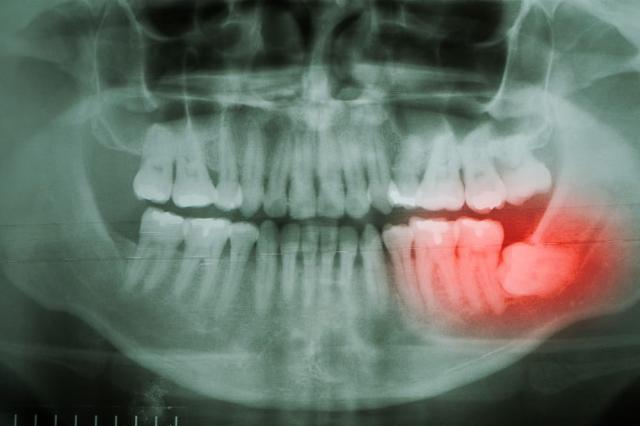

Kondisi tersebut sering kali membuat gigi bungsu justru tumbuh ke samping sehingga mendorong gigi di depannya serta merusak saraf dan tulang di sekitar.

Dalam dunia medis, pertumbuhan wisdom teeth yang tidak sesuai posisinya disebut dengan impaksi gigi bungsu.

Bukan hanya nyeri, wisdom teeth yang tumbuh dalam posisi yang tidak normal juga bisa menyebabkan kerusakan gigi di sekitarnya.

Apabila posisi gigi bungsu Anda masih di dalam gusi, dokter akan melakukan rontgen gigi terlebih dahulu untuk menentukan apakah kondisinya perlu segera diatasi.